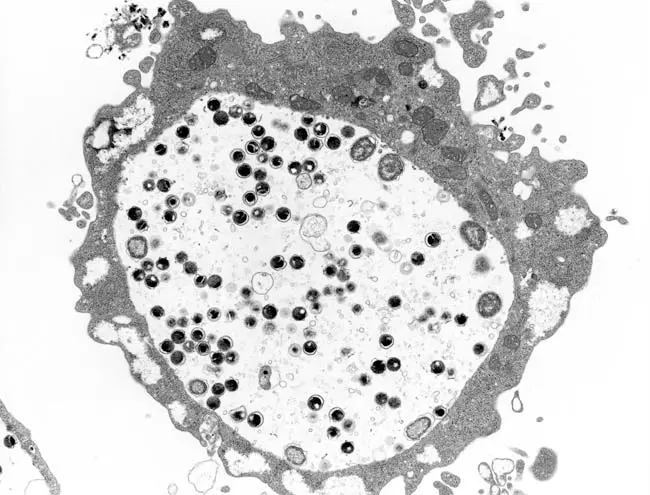

クラミジアは、ヒトをはじめとする動物細胞の中でのみ増殖する

「偏性細胞内寄生性細菌」と呼ばれる細菌です。